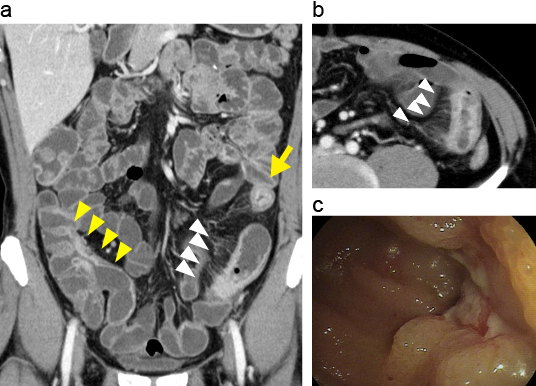

CTエンテログラフィーによる小腸病変

小腸・大腸型クローン病。

A. CT enterography(CTE)冠状断像。

B. CTE横断像。回腸末端部~上行結腸にかけて縦走潰瘍が形成され、同部位は腸管壁は強く造影され、直線化と層状化が認められる(黄矢頭)。さらに、口側の回腸に強い炎症部位では腸間膜直細動脈の拡張像(comb sign、白矢頭)とtarget sign(黄矢印)を認める。

C. 回腸末端部内視鏡像。縦走潰瘍を認める。